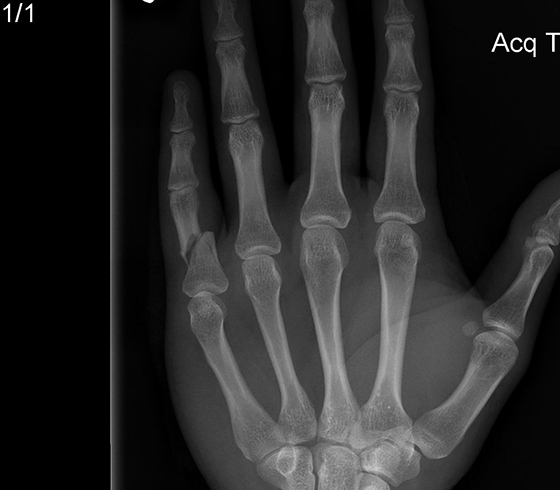

Фото: процедура диагностики различных повреждений пальцев рук и ног

Рентгенологический снимок со смещенными фрагментами кости пальца

Визуальное обследование не дает 100% результата. Подтвердить диагноз может только рентгеновский снимок. Именно это и предложат сделать пострадавшему сразу же после осмотра.